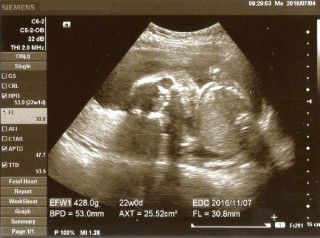

お医者さんから「性別って知りたい?」と聞かれましたが、既に私の目でも分かりました。お股に何もついてなーい!女の子の可能性が高いとのことです♪(*^▽^) 頭の大きさ:53.0mm、体重:428.0g 元気に育って大きくな~れ。 ※エコー写真は足ではなく顔です。